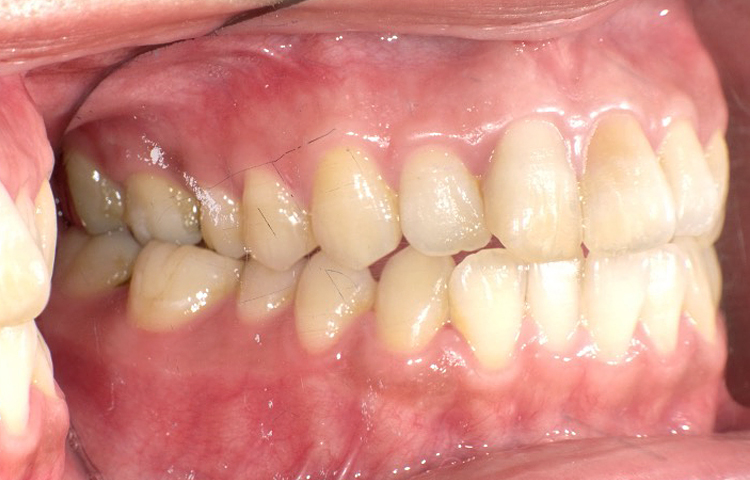

症例3

治療前

治療後

| 主訴 | 上下前歯全体の歯並びが気になる |

|---|---|

| 治療 期間 |

約6ヶ月 |

| 治療費 | 330,000円(税込)/調整費用別途 |

| 治療 内容 |

上下の前歯部にワイヤーを着けて進めていく、プチ矯正で施術。 |

| 治療の リスク |

固定の装置をつけないと後戻りしてしまう。 |